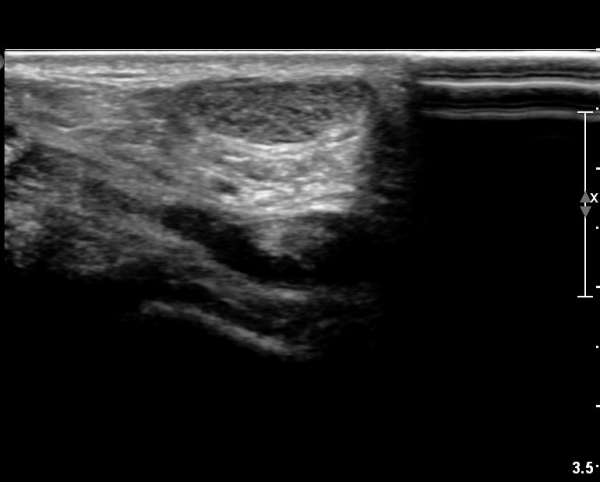

[¹ß¸ñ] simultaneosus tear of GCM and achiles tendon

abrupt leg pain developed during foot volleyball

he walk with severe limping with no weight bearing on rt. leg. on examination, there is local tendernes at GCM and achiles tendon, severe pain with ankle dorsiflexion.

ÃÊÀ½ÆÄ °Ë»ç